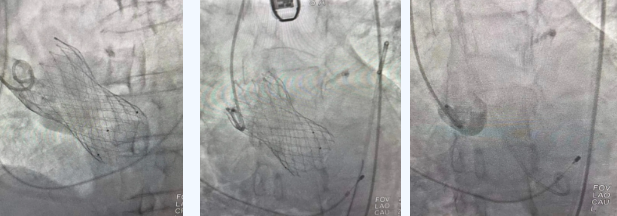

在麻醉手術(shù)中心的配合下,曾廣偉主任用導(dǎo)管經(jīng)股動(dòng)脈鞘進(jìn)入主動(dòng)脈瓣目標(biāo)位置,經(jīng)豬尾導(dǎo)管造影可見主動(dòng)脈瓣大量返流,因左室流出道較寬,大于瓣膜落腳點(diǎn)直徑,瓣膜釋放位置選擇及釋放難度極大。更為關(guān)鍵的是,患者常規(guī)四個(gè)錨定點(diǎn)只有一個(gè)可以用,定位要極其精準(zhǔn)才能保證瓣膜釋放后牢靠,同時(shí)不能有大的殘余瘺!稍有移位可能就需要再次植入瓣中瓣或者開刀!

術(shù)中,曾廣偉主任團(tuán)隊(duì)高效配合,完成了特定時(shí)間點(diǎn)起搏心臟、臨時(shí)短時(shí)間關(guān)閉呼吸機(jī)、降低主動(dòng)脈瓣阻力、快速釋放瓣膜等一系列高難度操作,有效保證瓣膜精準(zhǔn)釋放。瓣膜釋放經(jīng)TEE確認(rèn),主動(dòng)脈瓣膜釋放位置佳,經(jīng)豬尾導(dǎo)管造影,主動(dòng)脈瓣返流即刻消失,且無瓣周瘺。